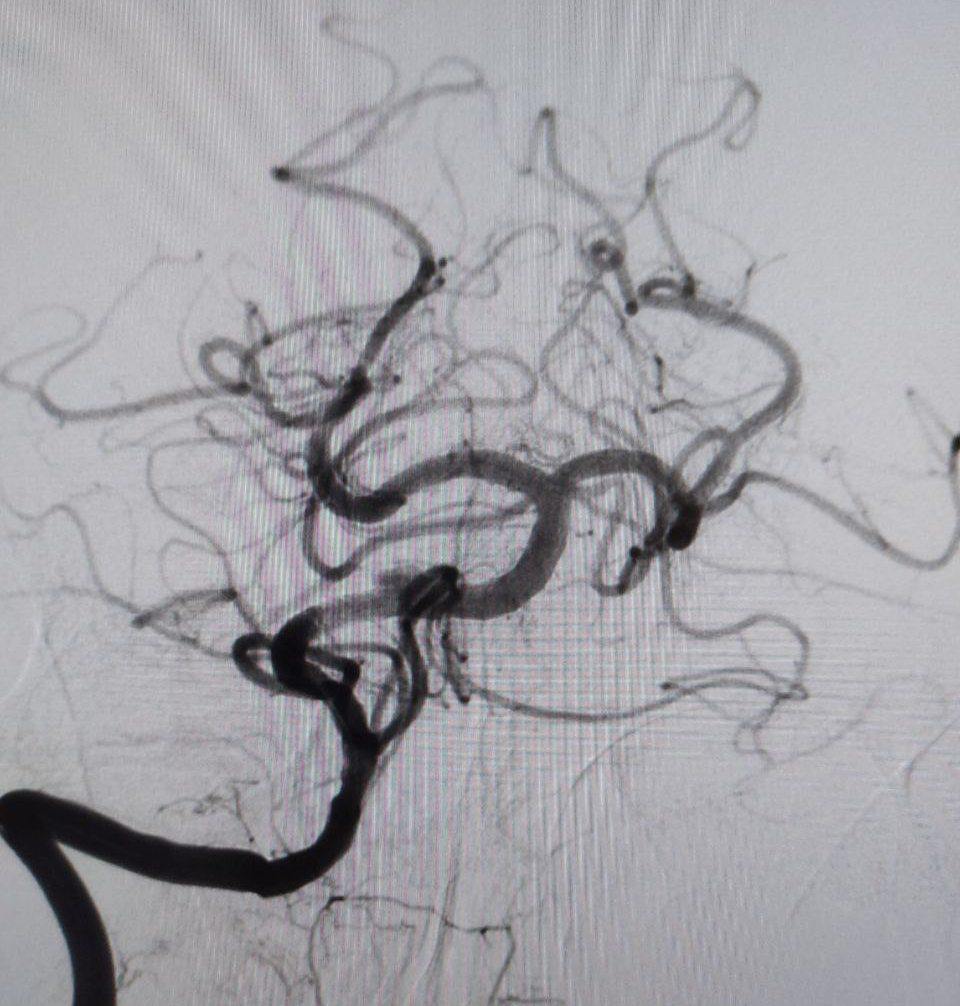

«В ходе обследования врачи диагностировали закупорку основной артерии, обеспечивающий кровоснабжение важнейших отделов головного мозга. Это очень тяжелое состояние с крайне высокой летальностью», — пояснили врачи.

Мужчине провели экстренную операцию, в ходе которой удалили тромб и установили стент.